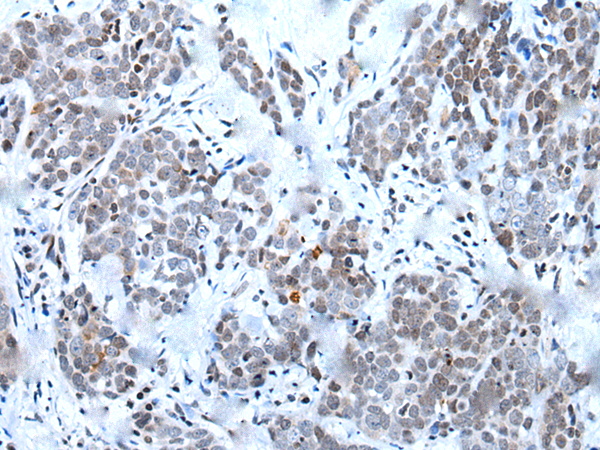

分类: 科研抗体货号: P12859别名: YB1; BP-8; CSDB; DBPB; YB-1; CBF-A; CSDA2; EFI-A; NSEP1; NSEP-1; MDR-NF1应用: IHC反应种属: Human, Mouse, Rat